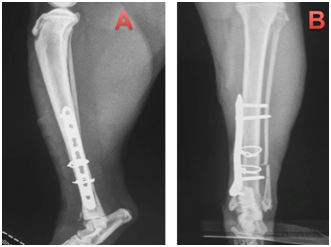

This paper reports the use of a combination of cerclage wire and a neutralization plate in two cats, resulting in primary bone healing. Two non-pedigree male cats (cat 1 and 2), cat 1 weighing 4.1kg and cat 2 weighing 3.9kg, were presented at the Veterinary Hospital of the Federal Univer- sity of Paraná following automobile trauma. General physical examination was unremarkable apart form orthopedic abnormalities. On orthopedic examination, instability, pain and crepitatus were found in the distal region of left tibia and fibula, indicative of fracture. Ventrodorsal and right lateral thoracic radiographs (to rule out pulmonary contusion) were made as well as craniocaudal and lateral views of the tibial and left fibula processes. One cat was presented with a closed tibial fracture. Pre-operative radiographs showed long oblique fractures of the distal third of the tibial diaphysis. The radiographs of the affected limbs of animals 1 and 2, are (Figure 1) (Figure 2), respectively.

Figure 1 Cat 1, with diagnosis of oblique fracture in the distal region of the left tibia and transverse fracture in the left distal fibula.

1. Craniocaudal projection showing oblique fracture in the distal tibia.

2. Mid-lateral projection with oblique fracture visible in the distal tibia.